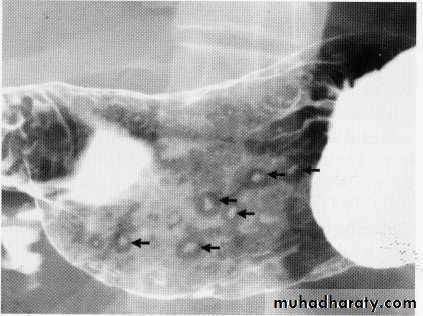

Advanced esophageal Ca